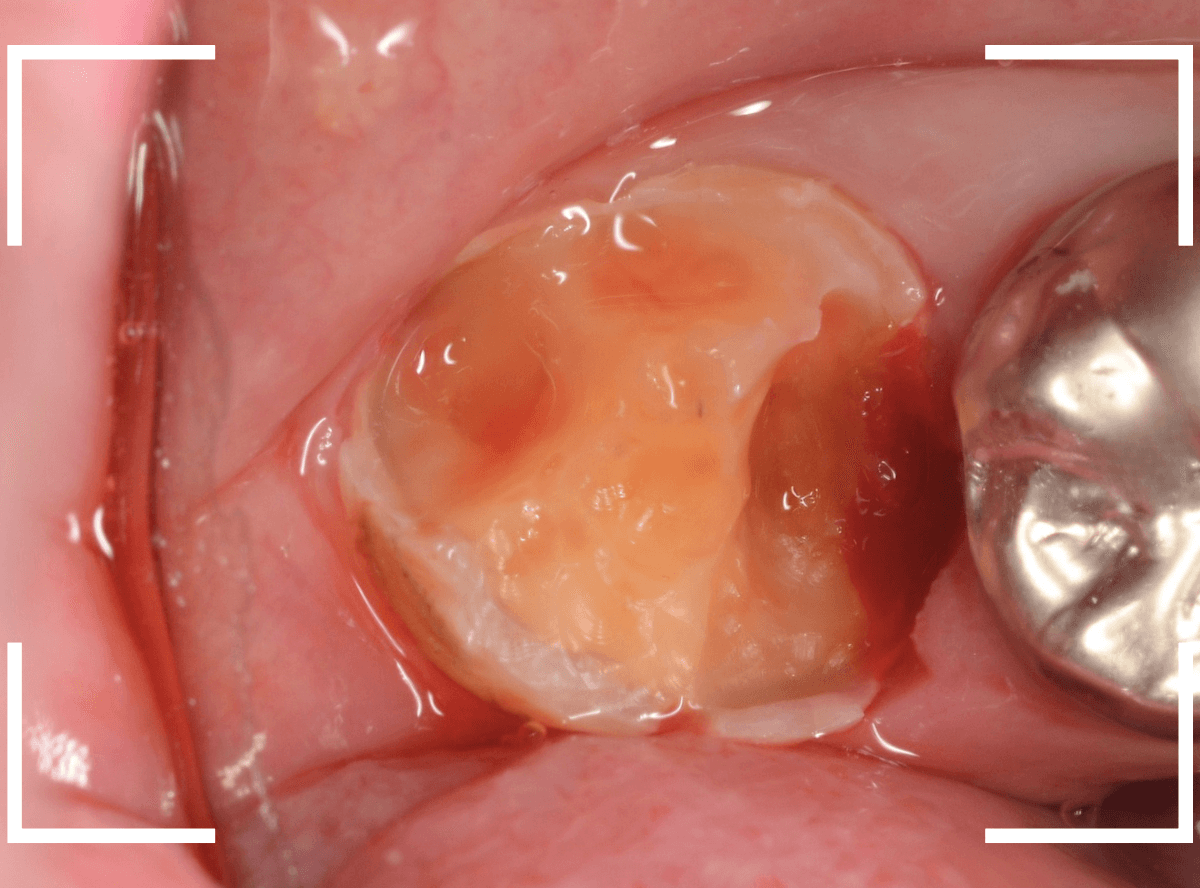

Case.12 下の一番奥の歯が、奥からひどい虫歯

「下の一番奥の歯が痛い」という訴えで来院された患者さんの例です。

一見では、特に問題ないように見えます。

レントゲン写真で確認します。

青いラインが歯の神経、赤いラインが虫歯です。

歯の奥の見えない部分から、大きな虫歯になっているのがわかります。

神経を除去しなければいけないかもしれないくらいの虫歯です。

治療を開始します。

歯の奥の部分を少し削ると、虫歯が出てきました。

慎重に虫歯を除去します。

歯肉ラインの下まで虫歯が進行しているため、虫歯の上に歯肉が広がっており、虫歯の見分けがつきづらい状況になっています。

虫歯を取り残さないように、余分な歯肉を除去します。

電気メスで、虫歯周囲の歯肉を除去後、全ての虫歯を除去しました。

虫歯は深かったですが、なんとか神経寸前のところで食い止められました。

神経を保護するお薬をつめて、セメントで蓋をしてしばらく経過観察します。

経過観察後、痛みがない事が確認できれば、つめものを作製します。